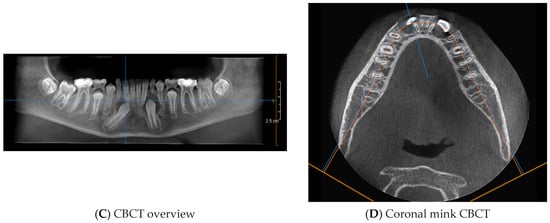

4. Case Report

4.1. Phase 1: Initial Orthodontic Treatment

4.2. Phase 2: Surgical Technique

4.3. Orthodontic Traction

4.4. Phase 3: Final Orthodontic Treatment